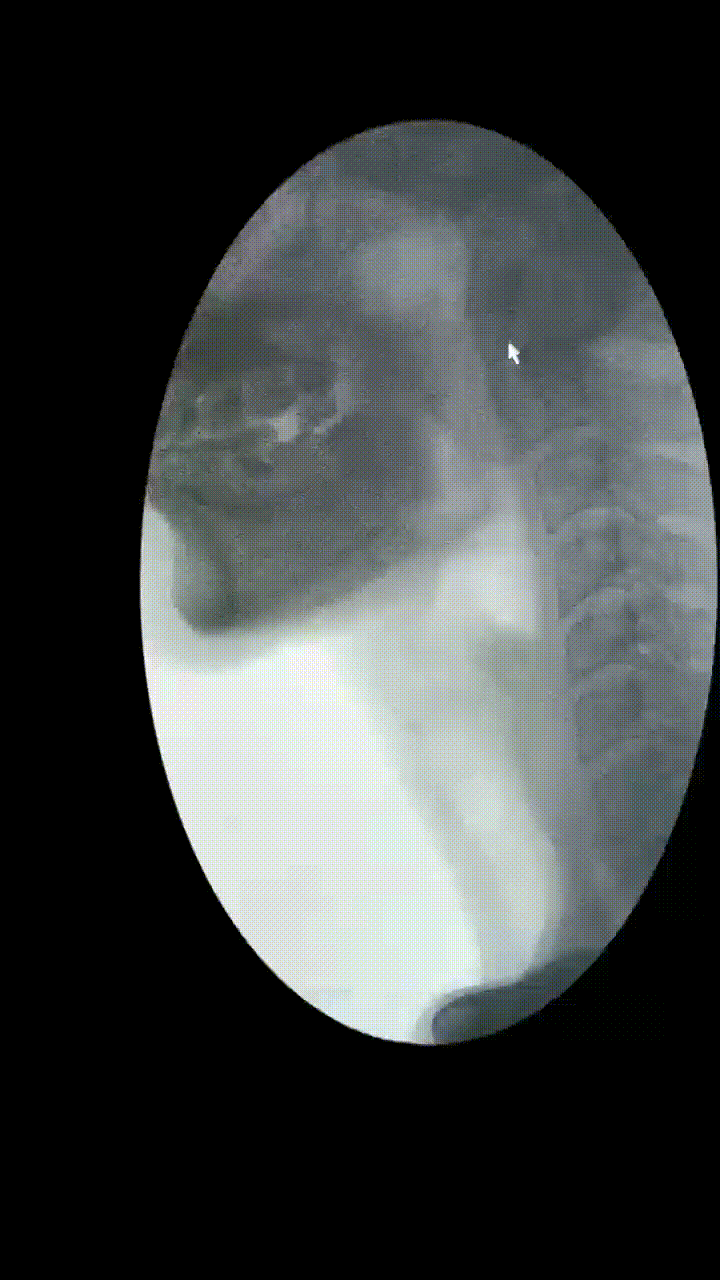

51岁的李先生(化名)10余年前接受鼻咽癌放疗,近2年反复出现饮水呛咳,进食困难,尤其进食固体食物时梗阻感明显,须“水捞饭”才能勉强进食。更为严重的是,这一年他已经经历了两次重症肺炎(CT见下图),差点进了ICU。张先生百思不得其解,在呼吸科医生的推荐下,来到了康复医学科门诊。

通过吞咽造影检查,李先生的问题终于“水落石穿”——是“吞咽障碍”惹的祸!

▲李先生存在环咽肌开放不完全,会厌谷和梨状窦大量残留,并且存在明显误吸,因此导致反复重症肺部感染。